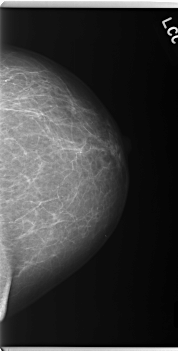

C_0159_1.LEFT_CC

LEFT_CC LINES 5952 PIXELS_PER_LINE 3024 BITS_PER_PIXEL 12 RESOLUTION 50 NON_OVERLAY